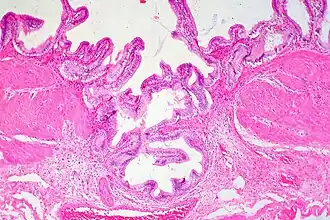

Rokitansky-Aschoff Sinus, Gallbladder Adenomyomatosis

Adenomyomatosis is frequently associated with gallstones and is often diagnosed incidentally, either from a cholecystectomy specimen or autopsy.[4][5][6] No serologic test exists to specify adenomyomatosis and laboratory studies are often normal. Co-existing diseases like cholecystitis may result in abnormal test results, such as elevated levels of white blood cells (leukocytosis), liver enzymes (transaminitis), or bilirubin (hyperbilirubinemia).[5]

Ultrasound is the preferred initial diagnostic choice for suspected gallbladder disease. Several distinct features of adenomyomatosis are discernable using ultrasound, making it a reliable modality for diagnosis.[4][5][6] The most characteristic features seen on ultrasound are the Rokitansky-Aschoff sinuses, which present either as echogenic foci when filled with biliary sludge/gallstones or anechogenic foci when filled with normal bile.[4][5][6] Other key features that may be seen include wall thickening and ring-down artifacts known as "comet tails" (produced by reverberations of sound between the sinuses).[4][5][6] Ultrasound can also distinguish between diffuse, segmental, and localized variants of adenomyomatosis based on morphology.[5][6]

In some cases, gallbladder wall thickening may be seen on ultrasound but is poorly defined and lacking specificity, particularly if the characteristic Rokitansky-Aschoff sinuses are not visualized. This can make it difficult to distinguish adenomyomatosis from other conditions that result in gallbladder wall thickening such as gallbladder cancer.[4][5][6] In these cases, MRI can prove helpful in providing the resolution needed for diagnosis. Especially effective is the T2-weighted MRI at visualizing the pathognomonic Rokitansky-Aschoff sinuses, which appear as round-shaped hyperintense cystic spaces that align in a curvilinear fashion along the gallbladder wall in a pattern described as the ”pearl necklace sign”.[4][5][6]